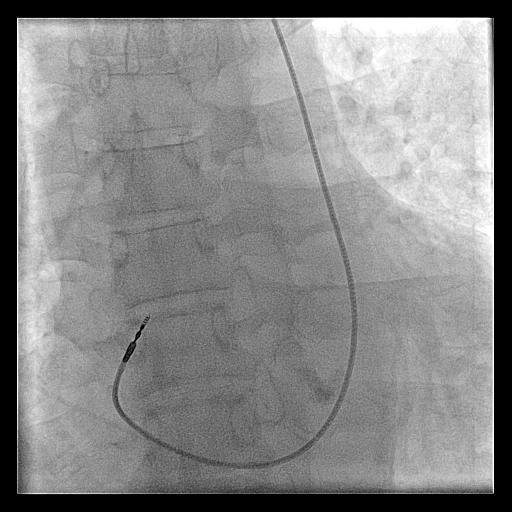

Unconventional access

• Internal jugular vein

• Femoral vein